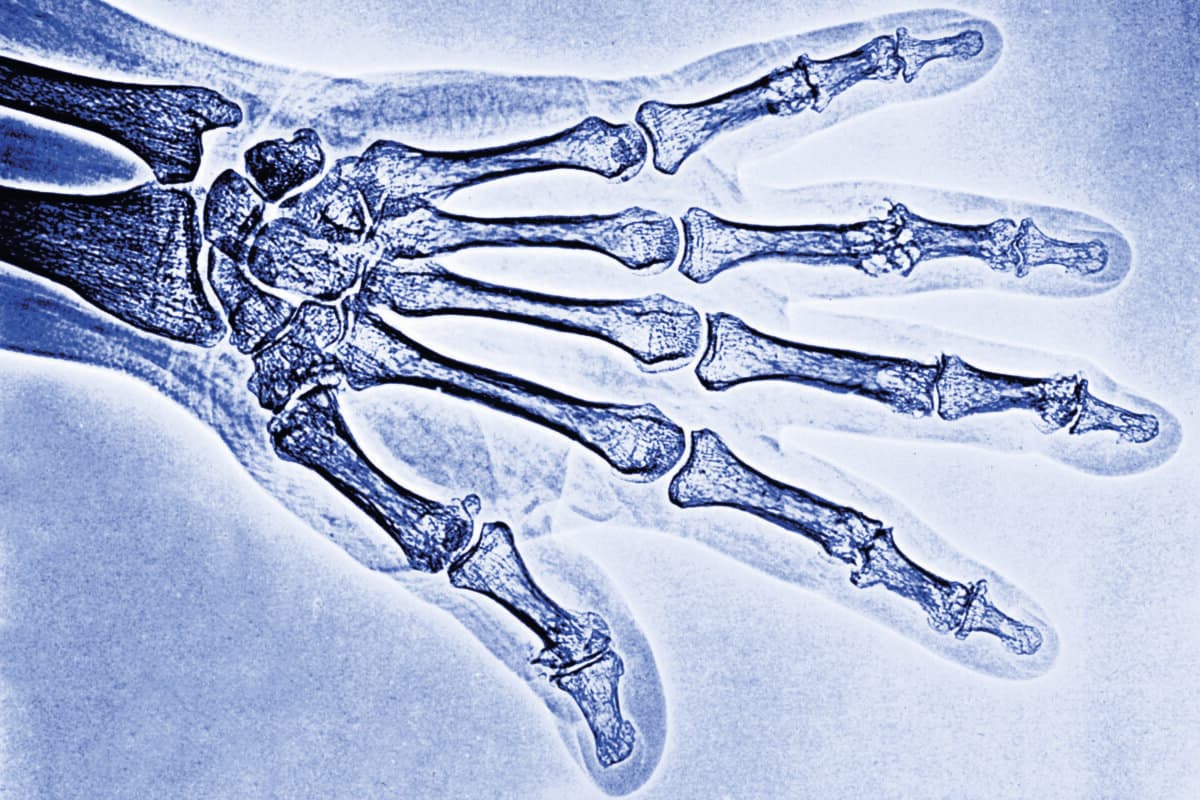

Arthrose de la main – vers une approche ciblée ?

Les options thérapeutiques de l’arthrose digitale sont toujours extrêmement limitées. Les options sont en grande partie réduites à des antalgiques. De nombreuses tentatives de traitements modificateurs de la maladie ont échoué. L’espoir existe toutefois de parvenir à des approches efficaces en définissant des endotypes et en sélectionnant mieux les patients.

L’arthrose des mains est une maladie rhumatismale très fréquente à laquelle on n’accorde cependant pas l’attention qu’elle mérite. Cela s’explique probablement par le fait que les options thérapeutiques restent très limitées.